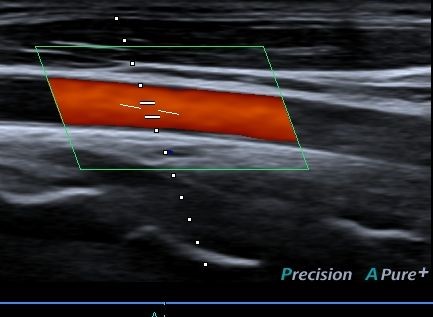

Doppler

O ultrassom com Doppler permite medir a quantidade de fluxo sanguíneo do corpo através de suas artérias e veias.